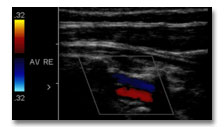

Duplex-Sonographie hirnversorgende Gefäße